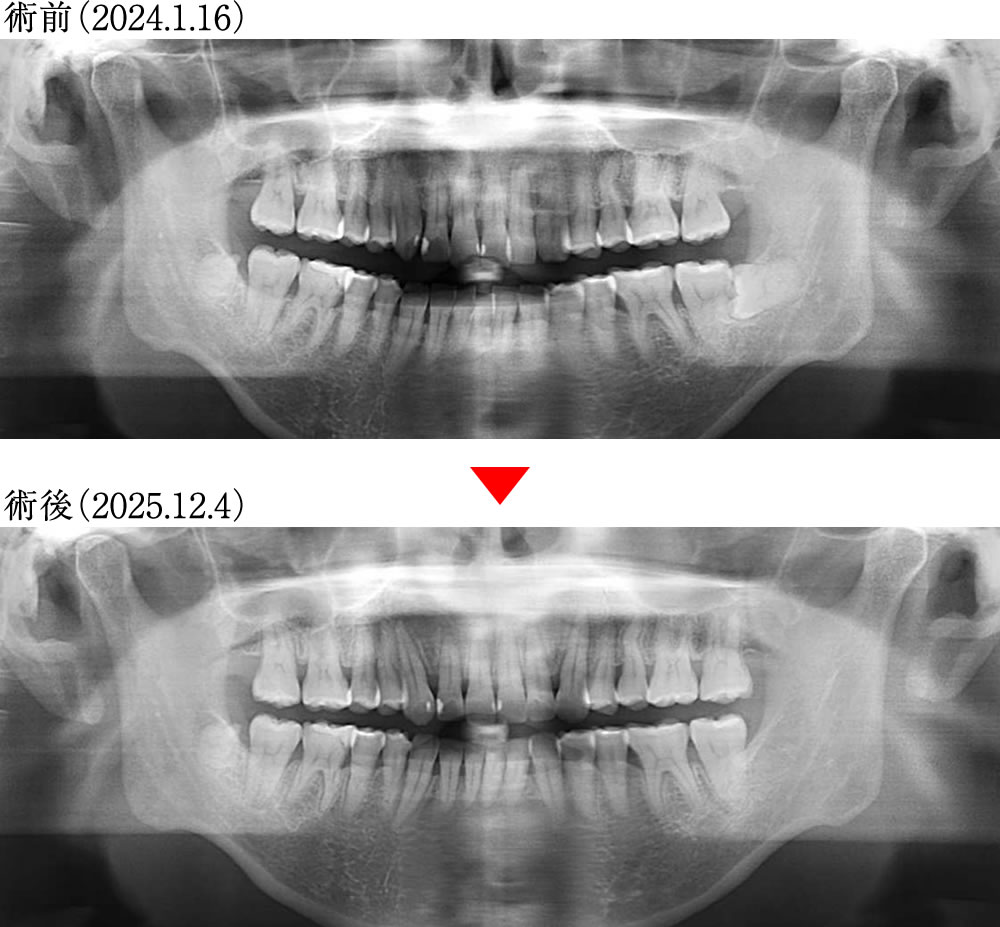

術前術後のレントゲン画像

歯根の吸収もなく、咬合平面が整いました。